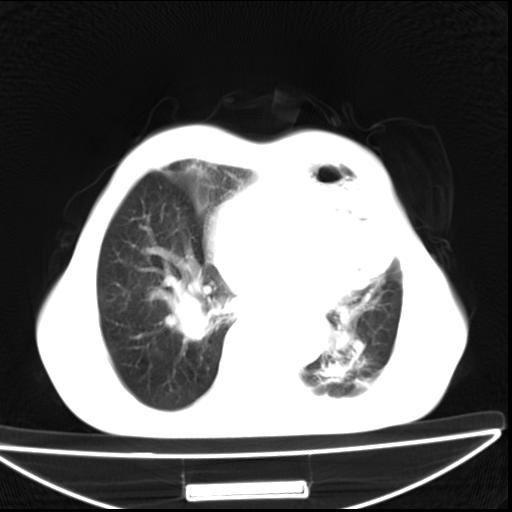

男  70岁,发烧咳嗽4天。盗汗,消瘦。无痰中带血丝,以前有肺tb病史,ct见,双肺tb,左侧胸廓塌陷,左胸膜肥厚粘连。纵隔移位,右侧胸腔积液,大家说说那个心影前左肺舌叶除了肺大炮还有炎症还是干酪性肺炎?有占位吗?我看纵隔淋巴结也大。

1)两肺继发性肺结核并左肺上叶肺不张,支气管扩张。2)双侧胸膜炎(胸膜增厚+少量胸腔积液)。

两肺继发性肺结核并感染,左肺上叶肺不张。建议ct增强。